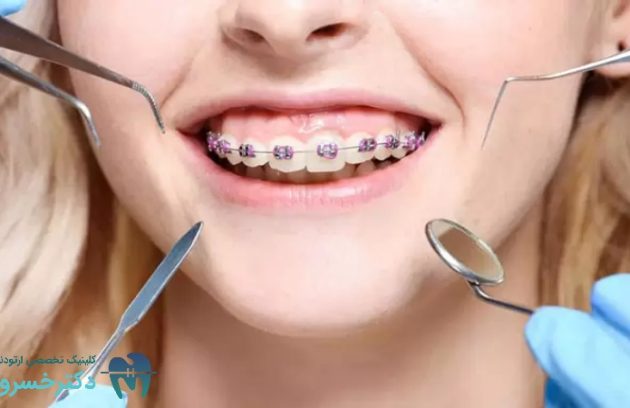

ارتودنسی فرآیندی است که در آن ظاهر دندان ها بهتر شده و عملکرد جویدن و تکلم نیز بهبود می یابد.…

چگونه ارتودنسی لبخند هالیوودی شما را تحقق میبخشد؟